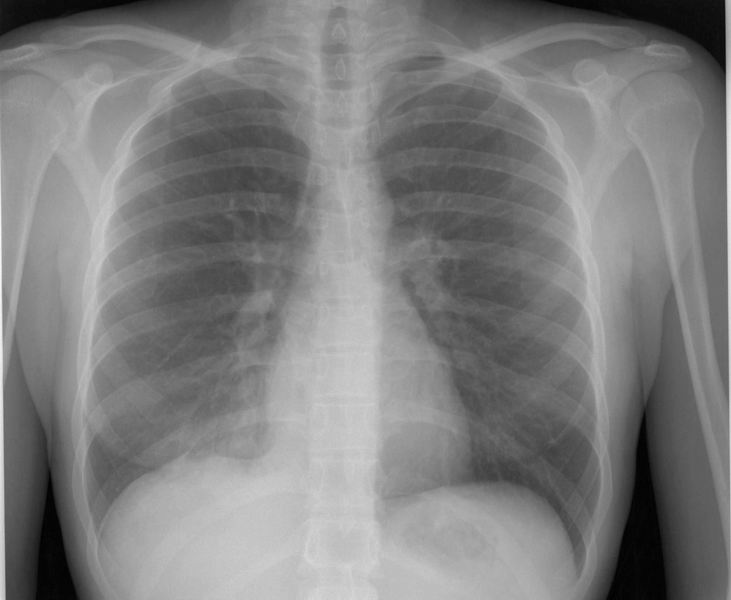

Thorax